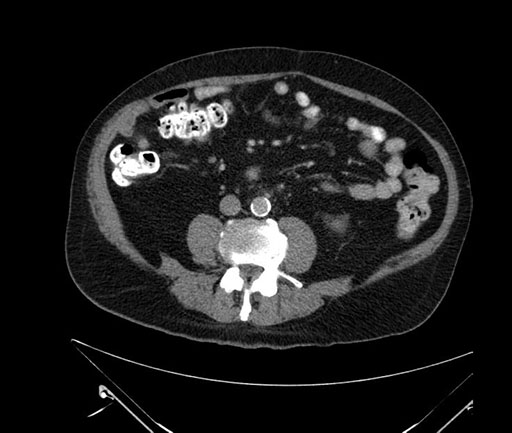

Whipple (pancreaticoduodenectomy) [case 7]

Axial - 3 months prior